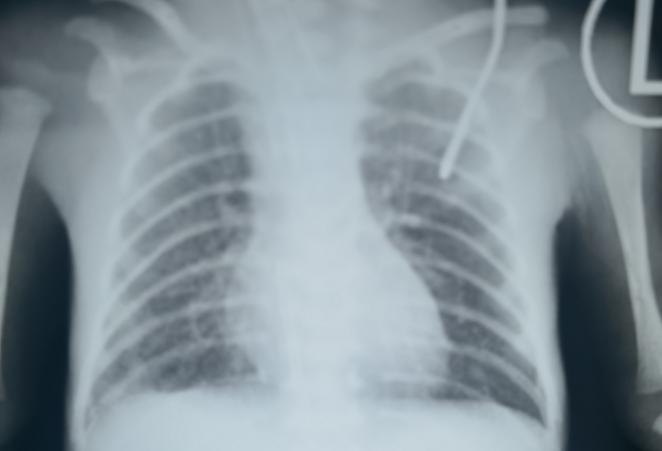

1月23日,当所有的人在欢度新春佳节时,王先生陪同怀孕27周的爱人来长沙走亲戚,结果爱人出现早产症状,提前在省妇幼分娩了。孩子胎龄小,生后出现呼吸困难,入住新生儿科。随后拍了胸片,医师告诉他孩子出现白肺,需要呼吸机来帮助通气,不然呼吸会很困难,甚至有生命危险。

早产儿早期的白肺,是因为肺发育不成熟,其肺表面活性物质不足导致进行性肺不张,生后数小时内气促等呼吸困难进行性加重,医学上称新生儿呼吸窘迫综合。该病一般多见于胎龄小于32周的早产儿。另外,如果孕母患妊娠期糖尿病、未发作行择期剖宫产、围产期窒息缺氧、重度血型不合溶血病、先天性基因缺陷等情况时,也会发病。

彭湘莲表示,白肺患者是新生儿重症监护病房的危急重症,往往需要气管插管,用呼吸机来帮助通气。随着NICU诊治能力的提高,经积极治疗,配合适宜的早产儿系统管理和监护后,多数患儿呼吸困难逐步缓解,呼吸机逐渐撤离。

(宝宝肺部治疗前和治疗后的照片。)